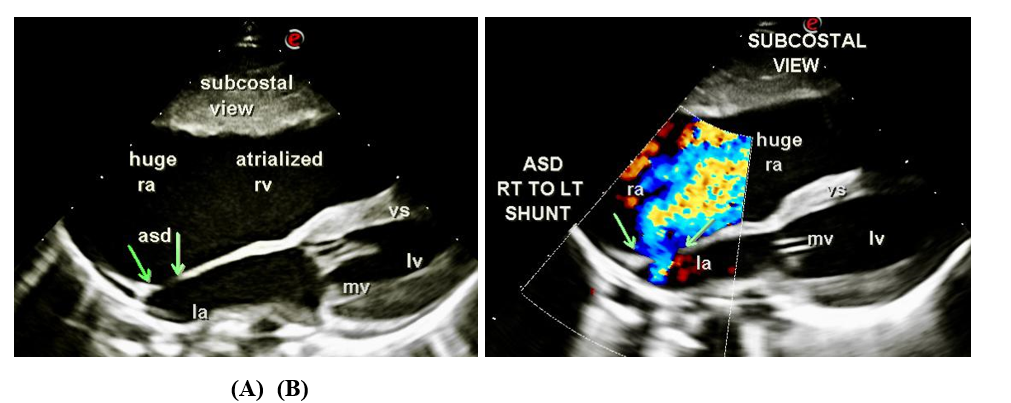

- Moderate ostium secundum ASD of size 4.5 mm with right to left shunt (Figure 2).

Figure 2: (A) Moderate size ostium secundum ASD detected in the subcostal view; (B) Right to left shunt demonstrated across ASD. ra, right atrium; rv, right ventricle; lv, left ventricle; mv, mitral valve; la, left atrium.